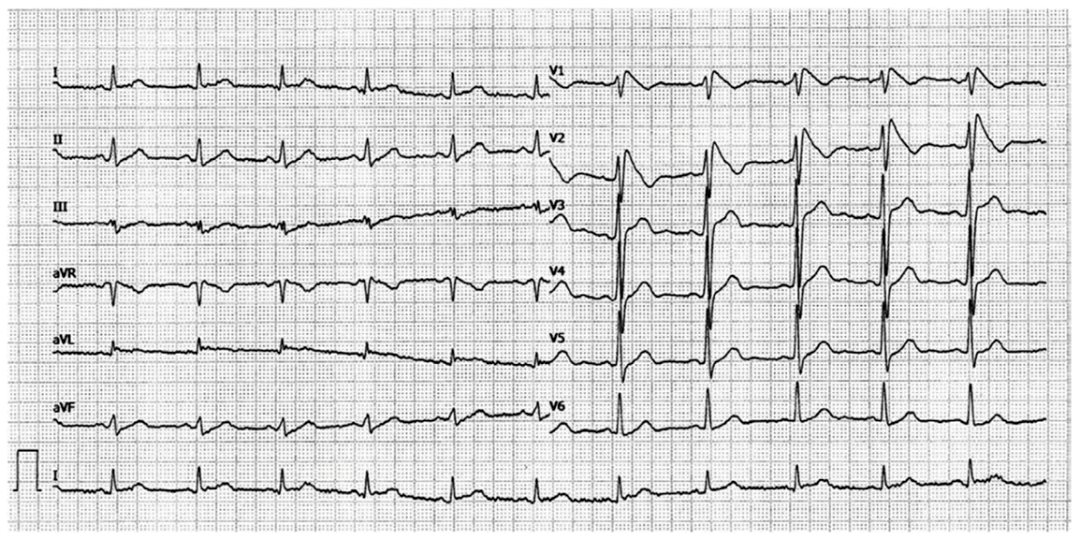

59岁的老先生 , 既往没有心脏病史 , 因突发心悸伴有头晕2小时于急诊就诊 , 他的心电图有点特别(图1) , RR间期绝对不齐 , 凌乱异常 , 却又是宽QRS波 。

图1:患者因头晕、心悸就诊 , 心电图提示宽QRS波心动过速 , RR间期绝对不齐